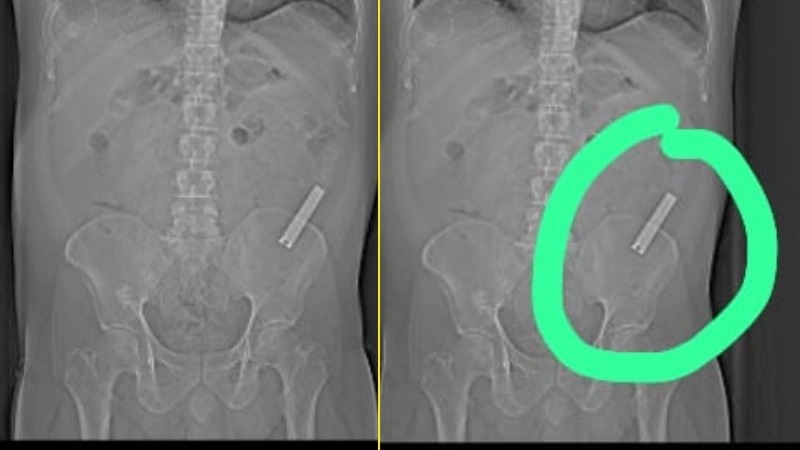

ಸರ್ಜಾಪುರದ 40 ವರ್ಷದ ನಿವಾಸಿಯೊಬ್ಬರು ಮದ್ಯಪಾನ ಅಮಲಿನಲ್ಲಿ ನೈಲ್ ಕಟ್ಟರ್ ಅನ್ನು 8 ವರ್ಷಗಳ ಹಿಂದೆ ನುಂಗಿದ್ದರು. ಇದನ್ನು ನುಂಗಿರುವುದೇ ವ್ಯಕ್ತಿ ಮರೆತು ಹೋಗಿದ್ದರು. ಮೊದ ಮೊದಲು ಇದು ಅಷ್ಟಾಗಿ ನೋವು ಕಾಣಿಸಿಕೊಂಡಿಲ್ಲ. ಆದ್ರೆ ಈಗೀಗ ಅದರ ನೋವು ವಿಪರೀತವಾಗಿತ್ತು. ಹೀಗಾಗಿ ಸ್ಥಳೀಯ ಕ್ಲಿನಿಕ್ಗೆ ದಾಖಲಾಗಿ ತಪಾಸಣೆ ಮಾಡಿಸಿಕೊಂಡಿದ್ದರು. ಆಗ ಸ್ಕ್ಯಾನಿಂಗ್ ವೇಳೆ ಹೊಟ್ಟೆಯಲ್ಲಿ ಏನೋ ಸಾಧನ ಇರುವುದು ಗೊತ್ತಾಗಿದೆ.ಇದರಿಂದ ಹೊಟ್ಟೆ ಒಳಗೆ ಏನೋ ಇದೆಯೆಂದು ಹೆಚ್ಚಿನ ಚಿಕಿತ್ಸೆ ಪಡೆಯಲು ವ್ಯಕ್ತಿ ತಕ್ಷಣ ನಗರದ ಮಣಿಪಾಲ್ ಆಸ್ಪತ್ರೆಗೆ ದಾಖಲಾಗಿದ್ದರು. ಆಸ್ಪತ್ರೆಯ ಡಾ.U. ಲೋಹಿತ್ ನೇತೃತ್ವದ ವೈದ್ಯರ ತಂಡ ಲ್ಯಾಪ್ರೋಸ್ಕೋಫಿಕ್ ಶಸ್ತ್ರಚಿಕಿತ್ಸೆಯನ್ನು ಯಶಸ್ವಿಯಾಗಿ ನೆರವೇರಿಸುವ ಮೂಲಕ ನೈಲ್ ಕಟ್ಟರ್ ಅನ್ನು ಹೊರ ತೆಗೆದಿದ್ದಾರೆ. ಸದ್ಯ ಆರೋಗ್ಯವಾಗಿರುವ ವ್ಯಕ್ತಿಯು ಡಿಸ್ಚಾರ್ಜ್ ಆಗಿ ಮನೆಗೆ ತೆರಳಿದ್ದಾರೆ.